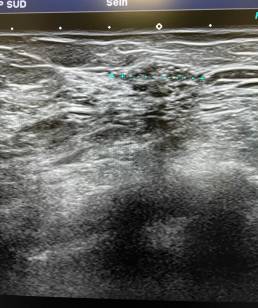

Ultrasound finds an oval formation at the union of the outer quadrants of the left breast containing microcalcifications.